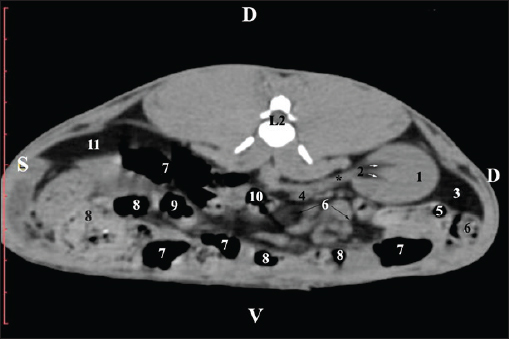

At the L2 level, the right kidney was in contact with the liver’s proc. caudatus, pars descendens of the duodenum, and the ileum. Pelvis renalis was a distinct hypoattenuated funnel-shaped soft tissue finding, whose narrow end pointed at the renal hilum and passed into the ureter. Recessus renalis was a clearly visible hypoattenuated widening of the central part of the renal pelvis in the dorsal and ventral directions (Figs. 4 and 5).

Fig. 4. Pre-contrast CT anatomical scan of the regio-abdominis media at the cranial L2 edge level. (1) Ren dexter; (2) pelvis renalis; (3) lobus caudatus (proc. caudatus) with visceral adipose tissue; (4) pars descendens of the duodenum; (5) ileum; (6) jejunum; (7) colon ascendens; (8) cecum; (9) colon transversum; (10) colon descendens; (11) lien; (12) pars transversa of the duodenum ; (*) ureter; (white arrow) recessus renalis.

Fig. 5. Pre-contrast computed tomography (CT) anatomical scan of the regio-abdominis media at the caudal L2 edge level. (1) Ren dexter; (2) pelvis renalis; (3) lobus caudatus (proc. caudatus) with visceral adipose tissue; (4) gl. adrenalis dextra; (5) ileum; (6) jejunum; (7) colon ascendens; (8) cecum; (9) colon transversum; (10) colon descendens; (11) lien; (*) ureter; (white arrow) recessus renalis.